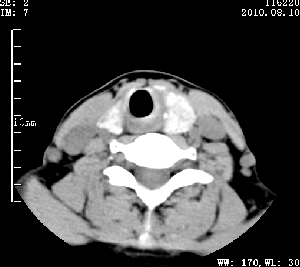

标题: CT28317:病人近几天无意间发现颈部肿块。 [打印本页]

标题: CT28317:病人近几天无意间发现颈部肿块。

甲状腺左叶局限性结节性甲状腺肿可能。建议增强扫描。

病变边界清楚,周围间隙清晰,甲状腺左叶(甲状旁腺?)肿大,右叶甲状腺腺瘤。

病变边界清楚,周围间隙清晰,左叶甲状腺肿大,右叶甲状腺小腺瘤。